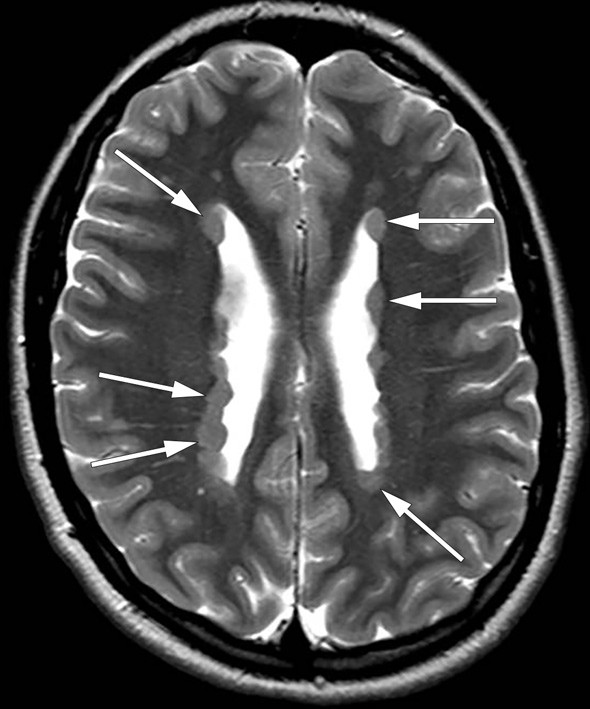

Standard elektroencefalogram (EEG) tatt etter overflyttingen var normalt, men magnetresonansundersøkelse (MR) av hodet etter epilepsiprotokoll viste utbredte forandringer. På bildet ser vi at aksial T2 gjennom øvre del av sideventriklene viser knuteformede formasjoner langs ventrikkelveggene. Funnene var forenlig med bilateral periventrikulær nodulær heterotopi.

Periventrikulær nodulær heterotopi er en migrasjonsforstyrrelse, det vil si en tilstand der cellevandringen under utviklingen av hjernen i fosterlivet ikke har funnet sted som forventet. Tilstanden oppstår mellom sjette og 24. svangerskapsuke og har ukjent insidens. «Heterotopi» refererer til forekomst av grupper med normale nevroner lokalisert på feil plass, i dette tilfellet grå substans som ikke har migrert til cortex cerebri, men blitt værende langs sideventriklene. Pasientene har som regel normal intelligens. Den vanligste manifestasjonen av periventrikulær nodulær heterotopi er epilepsi, som ses hos 80 – 90 %. Denne kan debutere i alle aldre (1, 2). EEG-registrering med dybdeelektroder hos pasienter med periventrikulær nodulær heterotopi og epilepsi har vist at malformasjonene i seg selv kan være epileptogene (1).